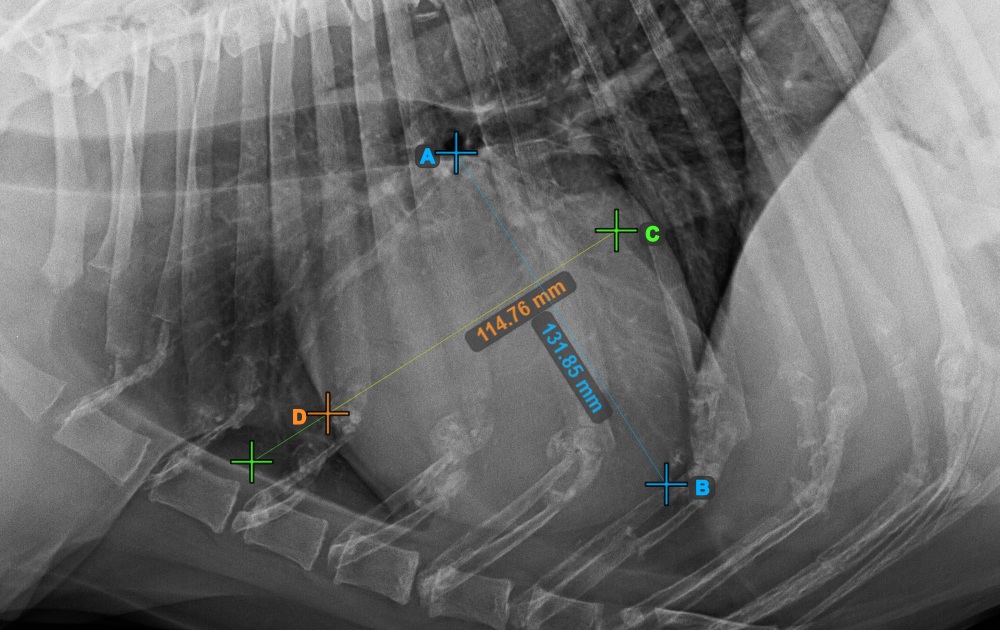

Identify the beginning of the T4 vertebra (the fourth vertebral body of the spine), counting from the initial point of the spine. Mark the beginning of the T4 vertebrae to continue the measurement. The software will draw lines from the marked point along the spine. The length of the lines depends on the measured long and short axes of the heart.

The image below represents the typical placement of the point at the beginning of the fourth vertebral body of the spine.